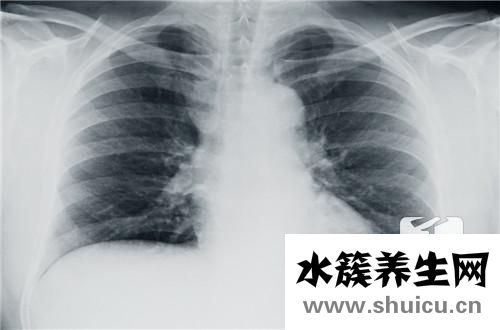

眾所周知,我們的胸腔總面積為一定的空白頁,而普通氣胸是指通過胸膜進入胸腔而引起擠壓的蒸汽。 氣胸屬于肺部疾病。 大多一些年輕人在男人中更常見。 根據胸腔鏡手術,可以減少蒸氣。 可是 盡管我不知道實際的術后復發多少錢,可是它手術治療的復發率很高,因此有很多癲癇發作原因應引起重視。

氣胸發作與治療方式相關。一般而言,單純性抽真空的保守治療者復發較高;選用胸腔引流管行閉式引流者,因為胸膜反應和胸膜粘連復發會有一定的減少,可是也會產生紊亂黏連的嚴重危害,可能引起更加難除的發作。醫師一般建議選用肺葉切除術微創手術醫治。肺葉切除術微創手術能夠完全摘除肺大皰,進而除根氣胸,使氣胸的復發減少到百分之一下列。使氣胸病人此后始終的道別氣胸發作,再次過上開心、健康的生活。

別稱難治性氣胸。它就是指肺臟基本X線檢查無法發覺顯著變病的身心健康者所產生的氣胸,多見于于年輕人,非常是男士高挑者。依據國外文獻報導,這類氣胸占自發性氣胸第一位,而中國則以繼發性氣胸主導。

其造成體制是在別的肺部疾病的基本上,產生肺大皰或立即損害胸膜增厚引發。常以漫性阻塞性肺氣腫肺氣腫或發炎后化學纖維疾病(如矽肺、漫性肺結核、局灶性肺間質纖維化工藝、囊性肺纖維化等)的基本上,細支氣管炎癥狹小、歪曲,造成活瓣體制而產生肺大皰。腫脹的氣腫泡因營養成分、循環系統阻礙而退行性病變性。

氣胸發病時患者均有呼吸不暢,其比較嚴重水平與發病的全過程、肺被縮小的水平和原來的肺功能檢查情況相關。在年青的吸氣作用一切正常的患者,可無顯著的呼吸不暢,即便肺被縮小》80%,亦僅能在活動時稍感胸悶氣短,而在身患漫性阻塞性肺氣腫肺氣腫的老年康復人,肺被輕微縮小就會有顯著的呼吸不暢。亞急性發病的氣胸,病癥可能更顯著,而漫性發病的氣胸,健側肺部能夠代償性澎漲,臨床表現可能會比較輕。